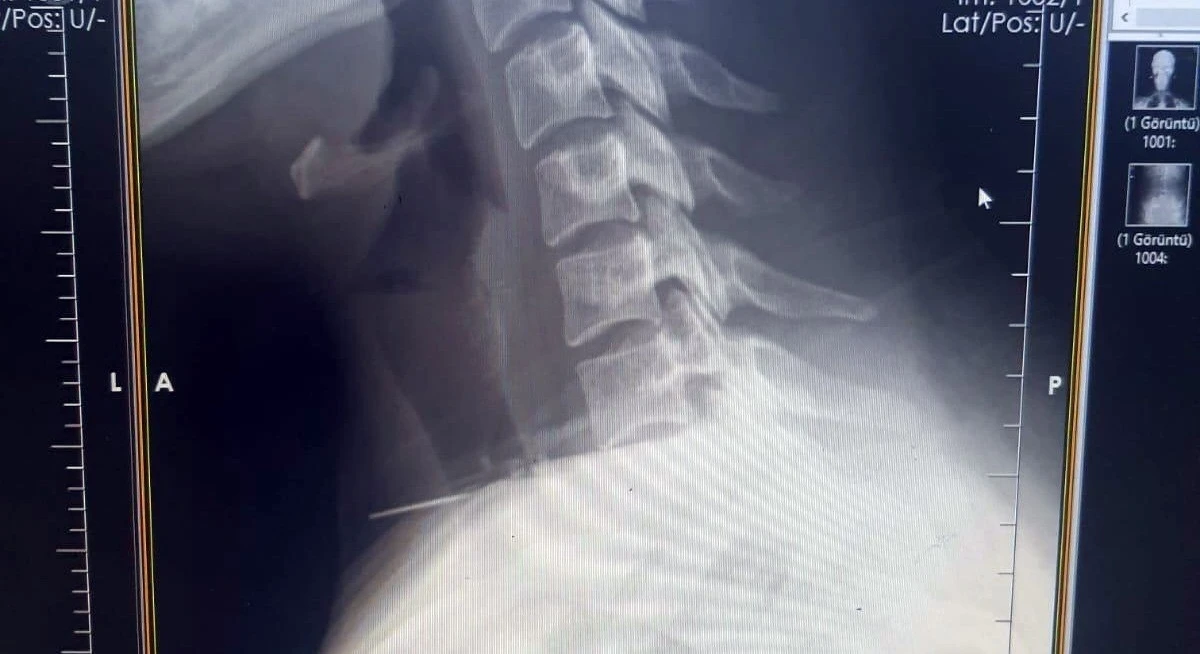

Edinilen bilgiye göre olay, Şanlıurfa’nın Birecik ilçesinde yaşandı. Boğazına dikiş iğnesi saplanan 25 yaşındaki Z.İ., Birecik Devlet Hastanesine başvurdu. Radyolojik incelemeler ve klinik değerlendirmeler sonucunda, 3 santimetrelik iğnenin boğaz bölgesinin derinliklerine doğru ilerlediği tespit edildi. İğne, yaklaşık 1 saat süren ameliyatla çıkarıldı. Ameliyat sonrası süreci sorunsuz atlatan hasta taburcu edildi.

Ameliyatı gerçekleştiren Birecik Devlet Hastanesi Kulak Burun Boğaz ve Baş Boyun Cerrahisi Uzmanı Dr. Rafet Yıldırım, boynuna iğne saplanan kadın hastayı başarılı bir operasyonla sağlığına kavuşturduklarını söyledi.